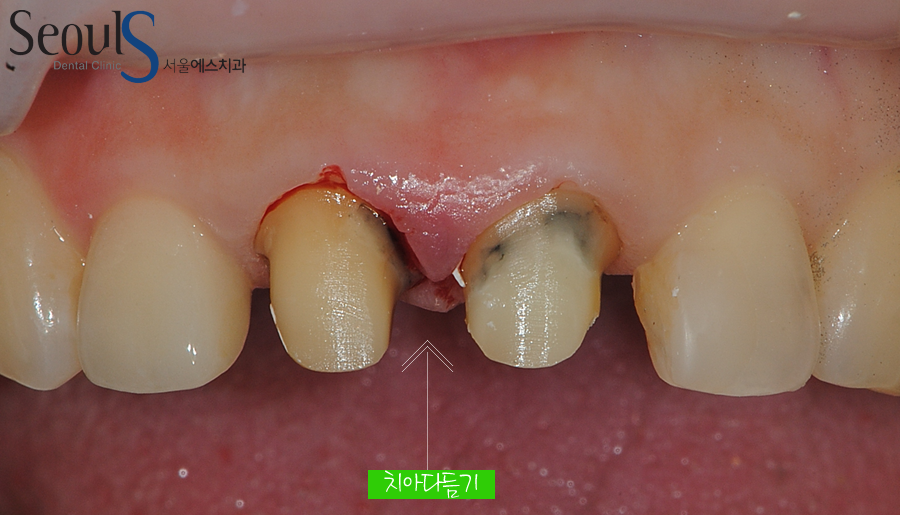

치아를 다듬었습니다